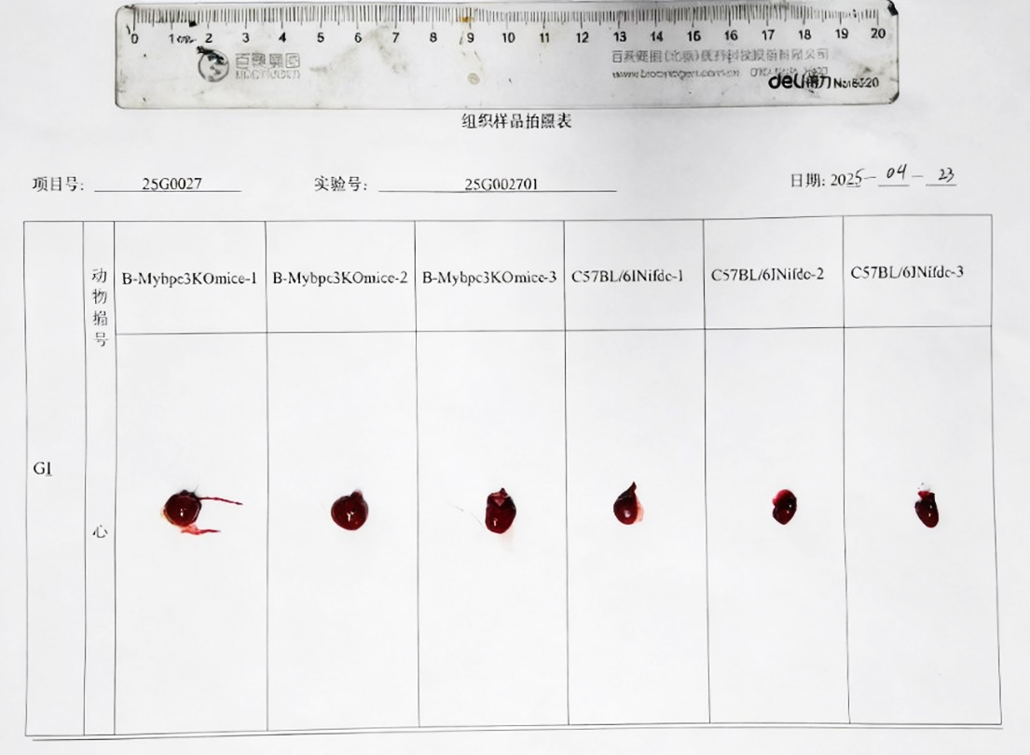

Size Comparison of Heart Tissues. Heart tissue was collected from wild-type C57BL/6JNifdc mice (male, 7-week-old, n=3) and homozygous B-Mybpc3 KO mice (male, 7-week-old, n=3). Heart from homozygous B-Mybpc3 KO mice is larger than that of wild-type mice.